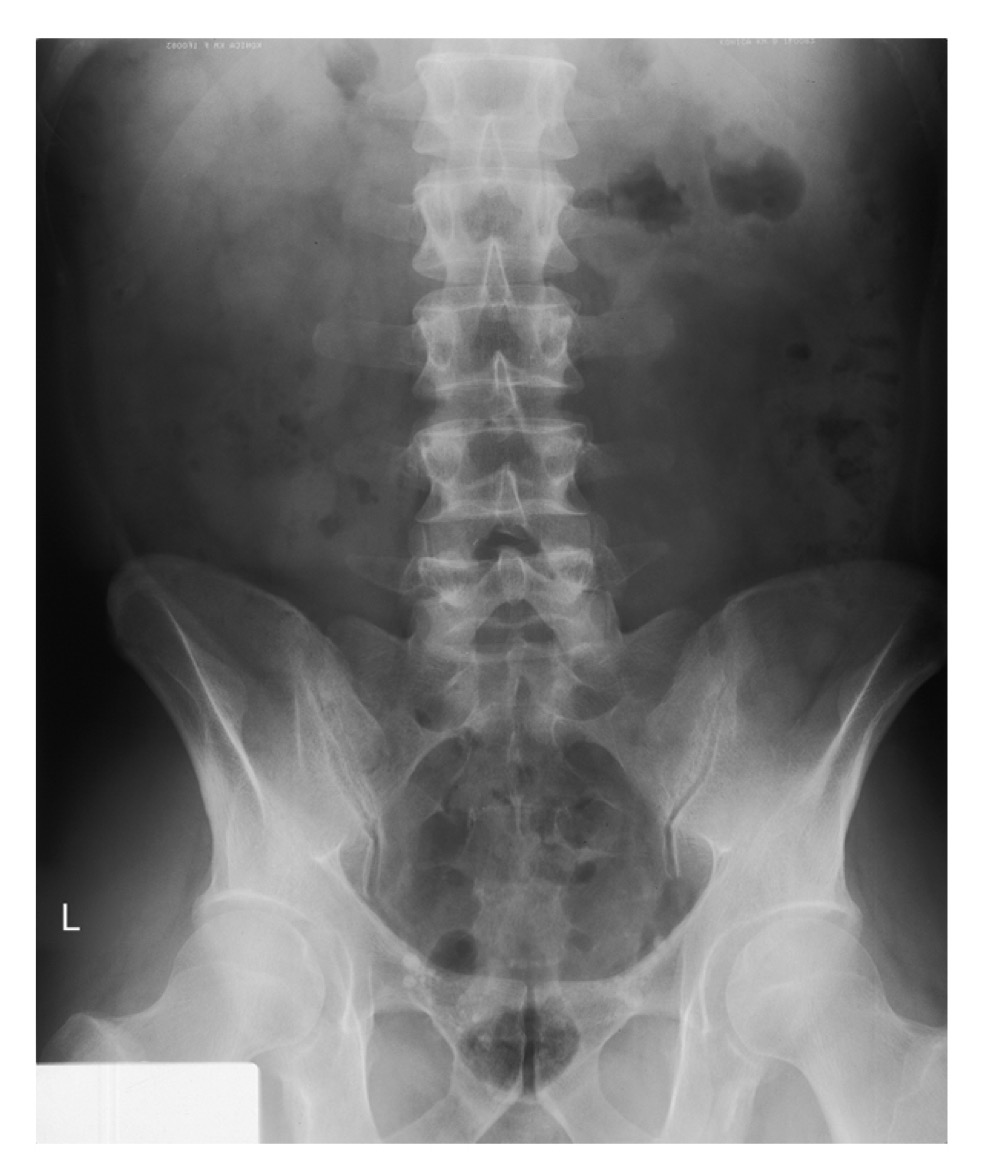

KUB (Kidney-Ureter-Bladder)

A radiographic view of the abdomen used to evaluate abdominal and urinary structures; may not show all structures, but helps visualize soft tissues and can indicate exposure quality (e.g., borders of psoas major muscles).

Psoas major

A large muscle of the posterior abdominal wall; its borders are visible on a properly exposed KUB and serve as a radiographic exposure indicator.

AP supine abdomen (KUB)

Anteroposterior view of the abdomen with the patient lying on their back; used in routine abdominal imaging.